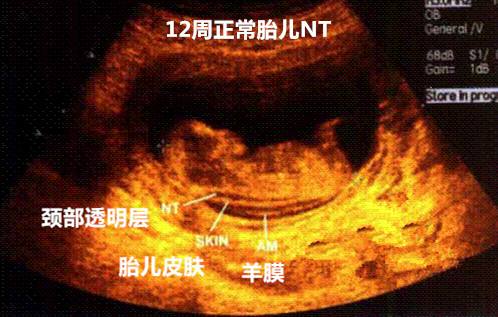

NT是nuchal translucency的缩写,指的是“颈项透明层”,也就是胎儿颈椎水平矢关切面皮肤至皮下软组织之间的厚度。NT检查就是针对这一指标的测定。

怀孕期间为什么要做NT检查呢?广州花都时代妇产医院产科主任介绍颈项透明层检查目的是为了在妊娠较早阶段诊断染色体疾病和发现多种原因造成的胎儿异常。因为研究发现,在怀孕11-14周期间,如果胎儿是唐氏儿或者是心脏发育不好的话颈项透明层会增厚。颈项透明层增厚与胎儿染色体核型、胎儿先天性心脏病以及其他结构畸形有关,颈项透明层越厚,胎儿异常的概率越大。 >>>点击此处【免费咨询】去哪里做NT检查好?

NT检查在怀孕11-14周做,超过14周检查会不明确,比唐氏综合症的时间较早。NT检查主要通过B超来进行测定,测量值小于3毫米为正常,超过3毫米则要考虑进行进一步检查,如羊水穿刺等。据有关资料统计,NT检查,然后再配合抽血化验,唐氏综合症的检出率能达到85%以上。>>>点击此处【免费咨询】NT检查多少钱?